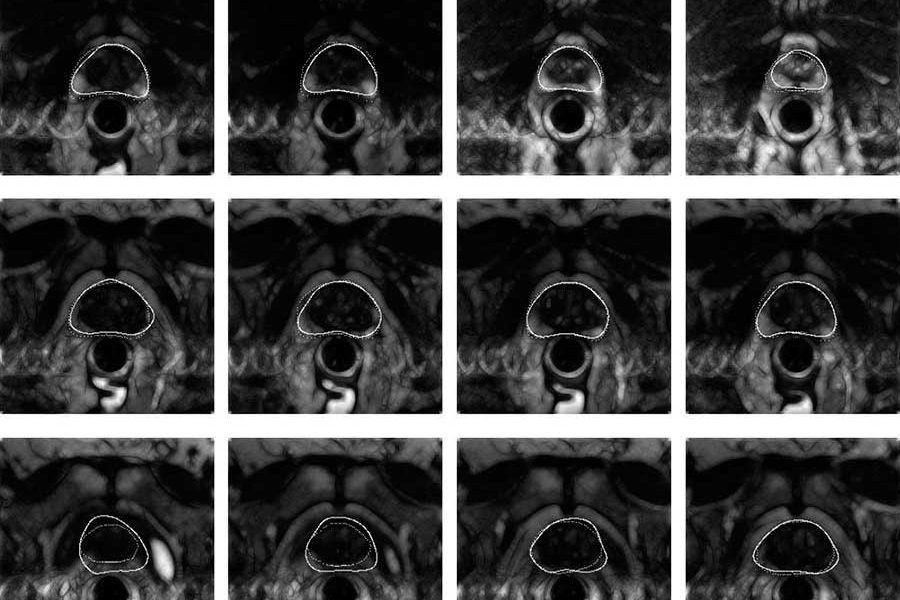

Доброкачественная гиперплазия предстательной железы (ДГПЖ) – нераковое увеличение простаты. Её развитие зависит от мужских гормонов: тестостерона и дигидротестостерона. Со временем болезнь той или иной степени тяжести поражает всех мужчин, даже тех, чьи яички и простаты нормально функционируют.

Доброкачественная гиперплазия простаты представляет собой один или несколько узелков, образовавшихся из железистого эпителия. Некоторые из них используют для дальнейшего развития стромальный компонент предстательной железы, но конечный результат всегда один и тот же – сдавливание мочеиспускательного канала.